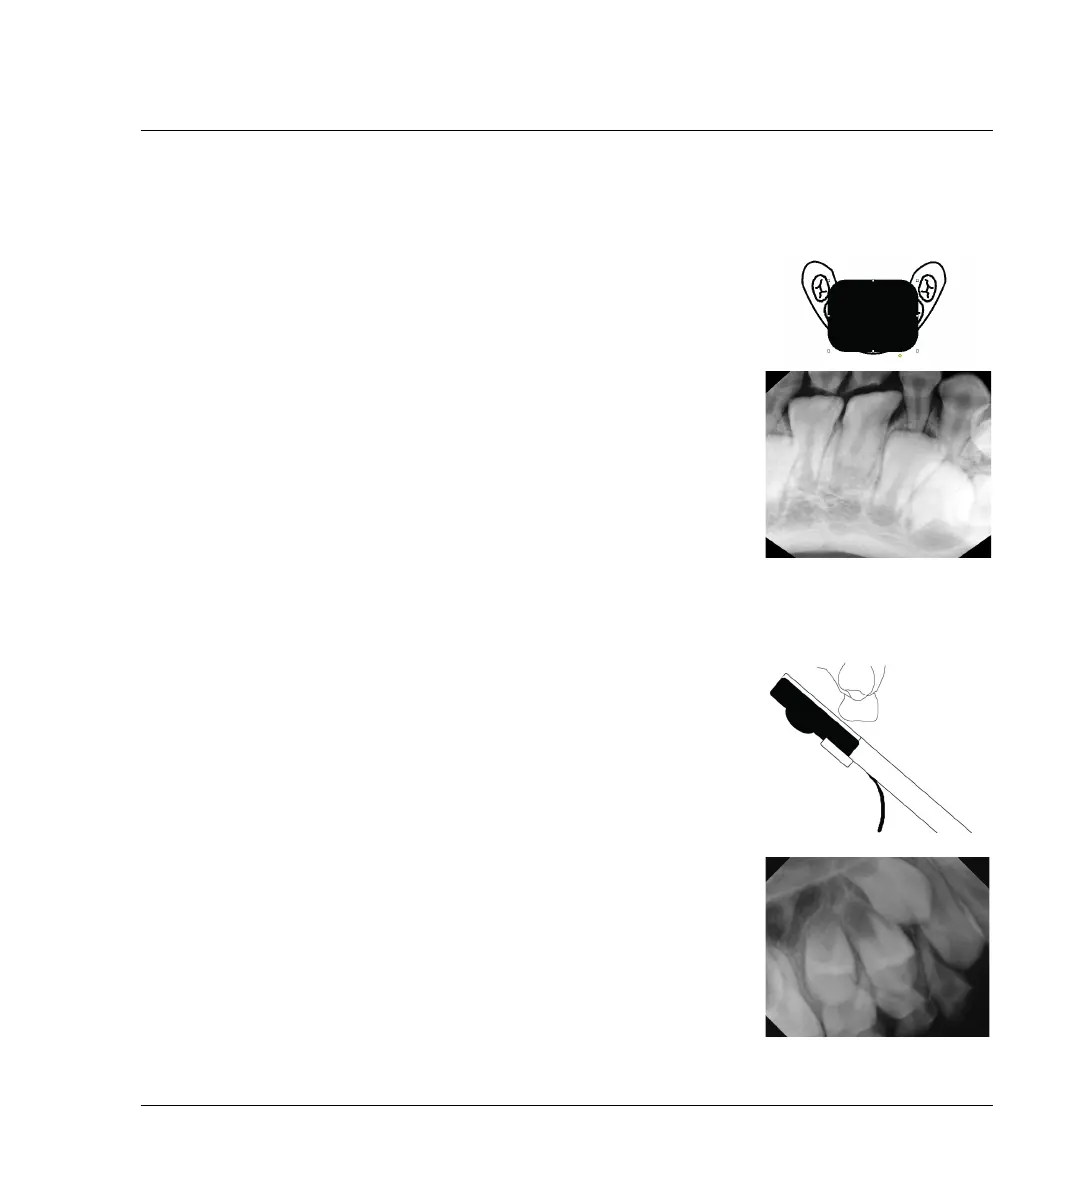

3.4.3 Occlusal X-rays

Occasionally, you may need an occlusal view.

Single-exposure Image

For a small child, you may be able to use the sensor placed lengthwise

from right to left and capture the necessary information in one exposure.

Bisecting-Angle Technique

Place the holder against the palate and use the standard Bisecting Angle

technique.